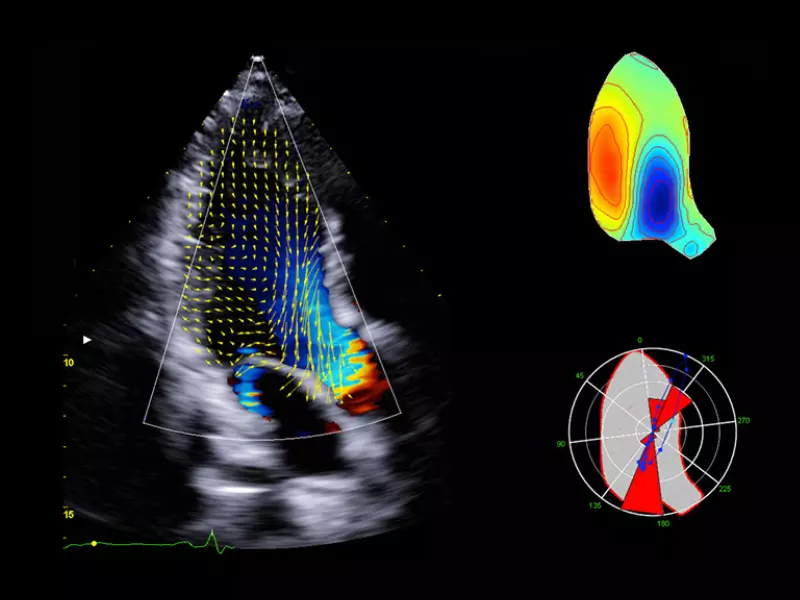

MyLab™9 Platform - XStrain™ 2D speckle tracking technologies for global and regional function

MyLab™9 Platform - XStrain™ 2D speckle tracking technologies for global and regional function